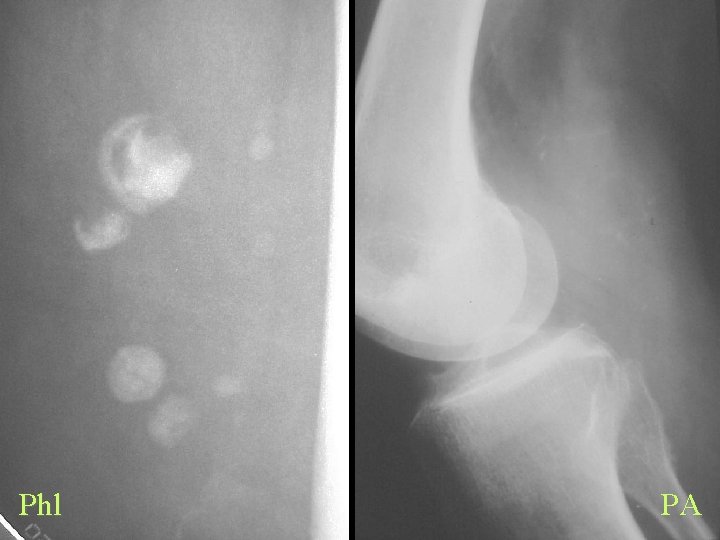

Calcification By Shape Linear and Curvilinear • Arterial – Atheroma, Aneurysm, Diabetes, HPT, Progeria, Werner’s • Nerve – Leprosy, Neurofibromatosis • Tendon and Ligament – Tendinitis, AS, Ochronosis, Fluorosis, Diabetes • Injection – Bismuth, Arsenic, Quinidine • Parasite – Cysticercosis, Guinea worm, Loa, Armillifer armillatus

Phl PA

Calcification By shape Some characteristic shapes • Circle or oval, lucentre – Phlebolith, Spherule, Cysterci • Reticulated – Dermatomyositis

ED Phl CC